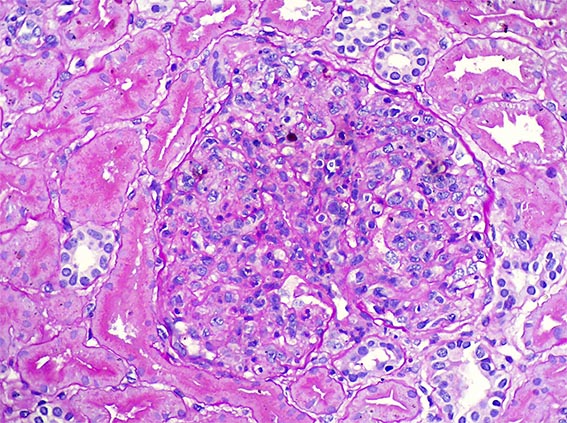

A 15-year-old woman with no medical history was evaluated by widespread edema, headache and coliuria. Blood pressure: 150/95. Hb: 12.7; Ht: 38.2% leukocytes: 9,800/mm2. Serum creatinine 1.9 mg/dL, BUN 29 mg/dL. Urinalysis: Proteins: 2.4 g/24h, erythrocytes: > 50/hpf, leukocytes: 4-5/hpf, nitrites: negative.

A renal biopsy was done, see the images.

Figure 2. H&E, X400.